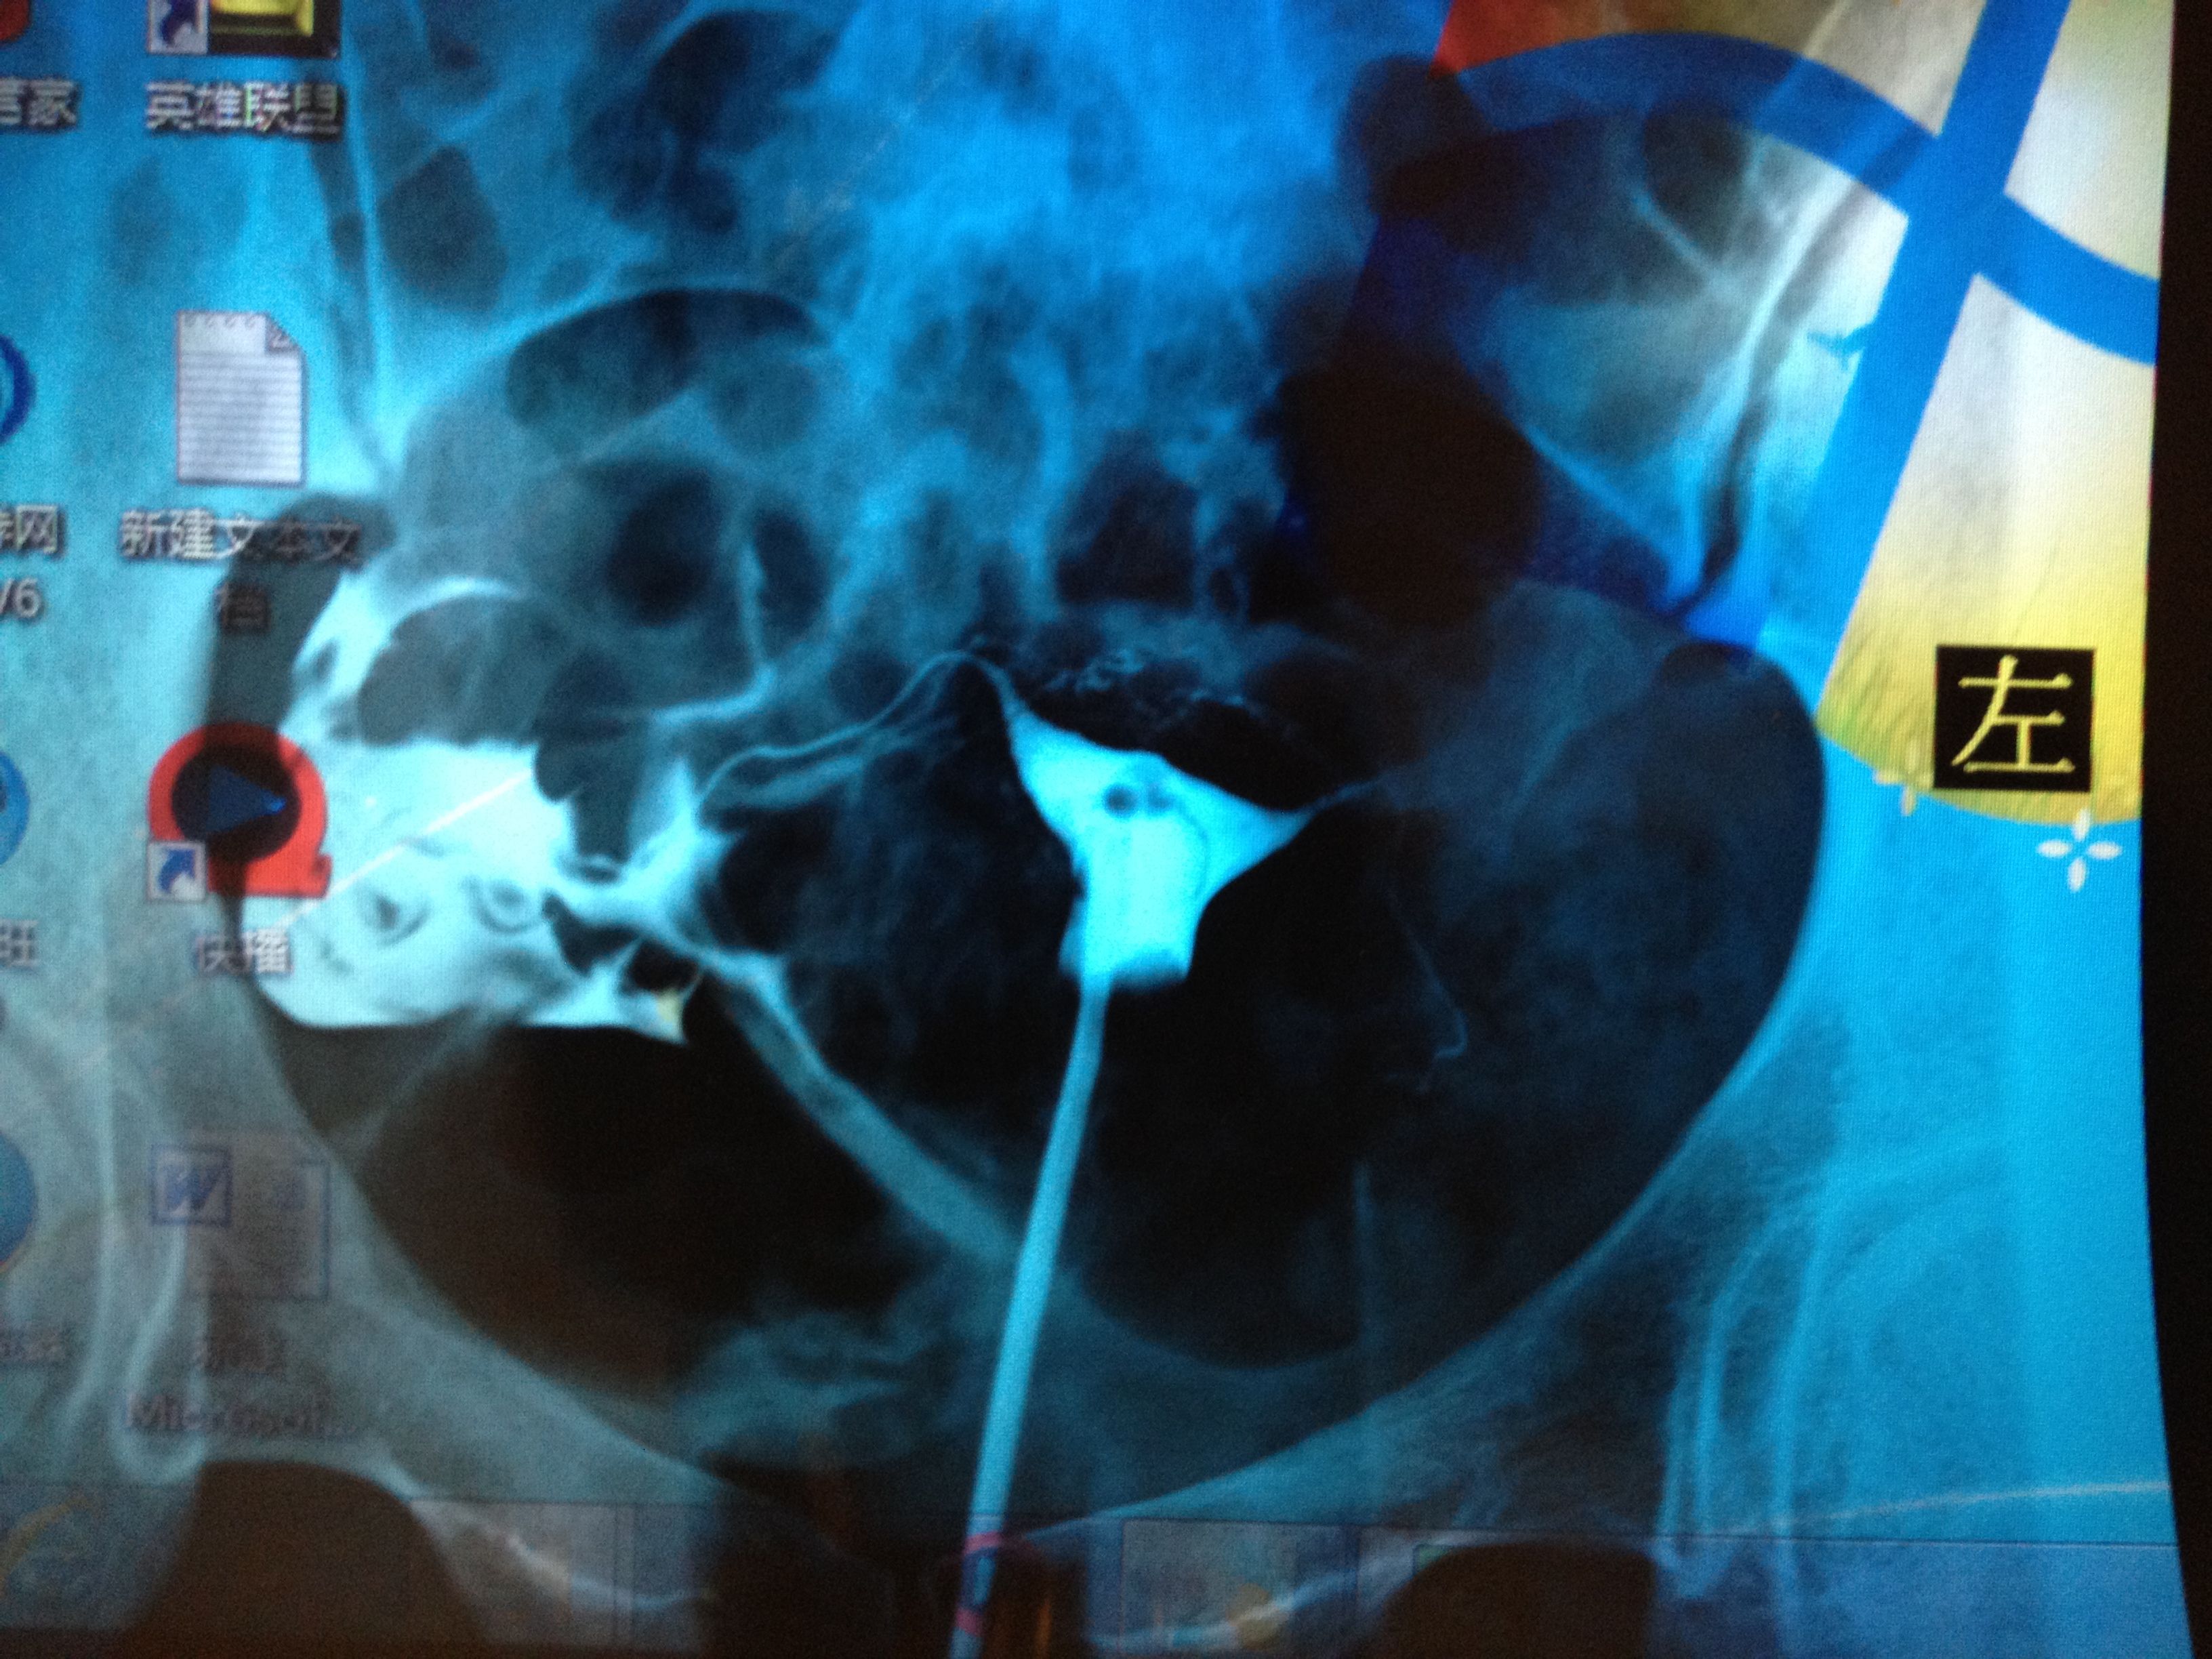

前面的影像是正常的,我就从左右侧描述说吧,两侧宫角充盈完整,右侧输卵管自宫旁连续显影,走行自然,光

滑,并见部分照影剂自该侧伞端溢入盆腔,并见少许弥散。左侧输卵管大致 显影至壶腹区附近,进一步注入照影剂未见任何进展。第三张片于盆腔内可见散在片絮状及条弧状照影剂影,弥散尚可以。医生说右侧细,可能有炎症,左侧不通,两侧都得通水,我想问问有通水的必要吗?还有我的右侧是不是良好的?还是有炎症,还有偏细?应该怎么治疗?前两张是刚开始的,后两张是20分钟后的。还有现在拿到抗精子化验单有一项是阳性?怎么办?还有那个准吗?